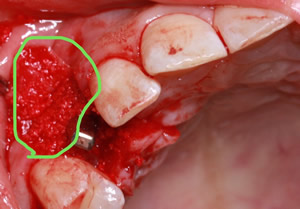

症例4

- 年齢・性別

- 60歳

- 治療期間

- 6ヶ月

- 抜歯

- 残根抜歯のみ

- 治療費

- 198万円

- 備考

- 右上5.6 右下5 左下4.5.6欠損

- 治療内容

- 6本のインプラントを右左側に2回に分けて埋入

- 施術の副作用(リスク)

- オペによる知覚障害。インプラントによる歯肉炎。インプラント脱落。